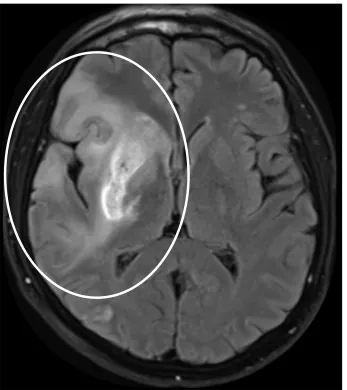

Magnetic Resonance Imaging (MRI)

MRI provides higher sensitivity and specificity than CT for diagnosing acute ischemic stroke (fig. 3). However, it is more time-consuming and not as readily available as CT. MR angiography can also be performed which is similar to CT angiography, and can help identify the location of the blood clot. MR angiography does not necessitate the injection of dye, however.

Figure 3: MRI of a patient with a stroke. The brighter region within the circle is the area affected by the stroke.